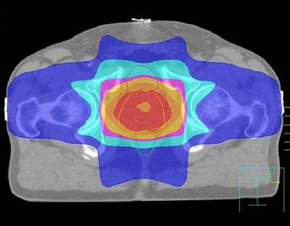

О суперсовременных, щадящих методах лечения рака рассказывают французские врачи. Радиотерапия в 3D-формате во Франции широко распространена.